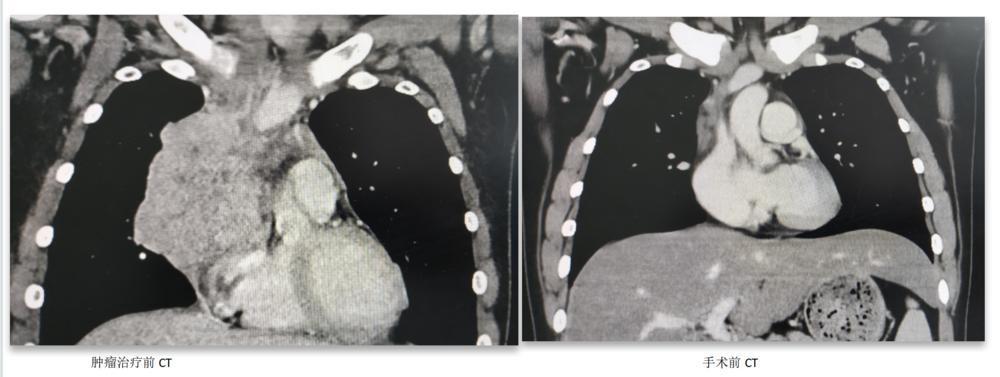

“即刻调整方案!” ,团队创新使用了新辅助治疗方案——给予小刘化疗联合免疫治疗以及抗血管生成治疗。2个疗程后,“奇迹”终于出现了,复查CT时,惊喜发现肿瘤显著缩小,临床评价为大部分缓解(PR)。但遗憾又接踵而至,继续使用该方案4个疗程,肿瘤不再进一步缩小了……

面对如此棘手的病情,医生团队再次召集涵盖心胸外科、肿瘤放射治疗科、肿瘤内科、麻醉科等为主的多个学科,进行细致研究和反复讨论,最终,敲定了小刘的治疗方案:药物治疗后,CT提示肿瘤与血管间隙清楚,纵隔淋巴结显著缩小,并且均可彻底切除,存在手术根治的机会,按诊疗规范,可进行根治性手术切除,术后根据病理缓解情况再确定术后辅助治疗方案。